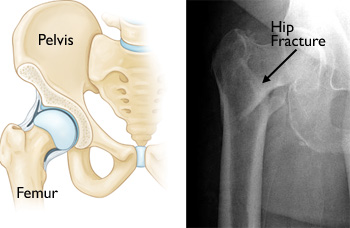

Hip fractures occur in the upper section of the femur (thighbone). The x-ray image on the right shows a hip fracture.

Hip fractures are breaks in the thighbone (femur) just below the hip joint. They are serious injuries that most often occur in people aged 65 and older.